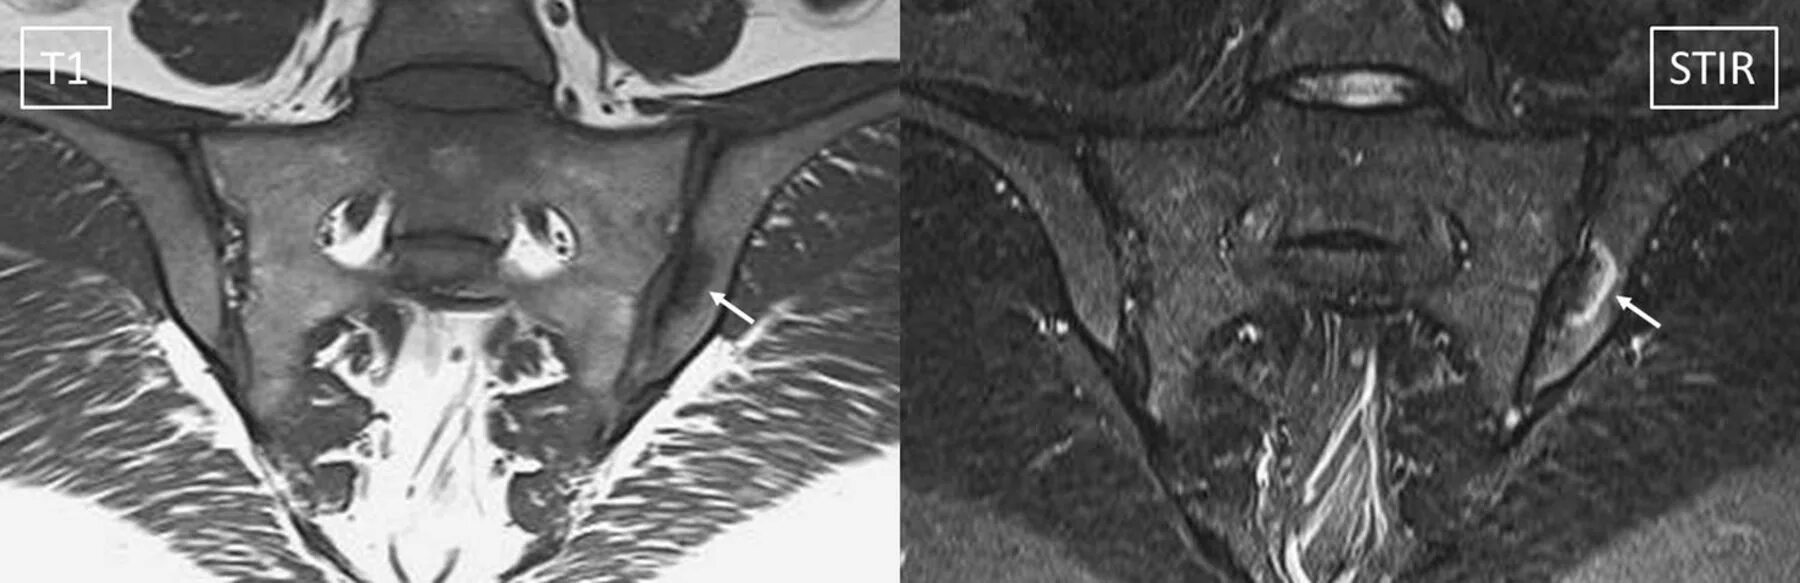

Сакроилеит на кт